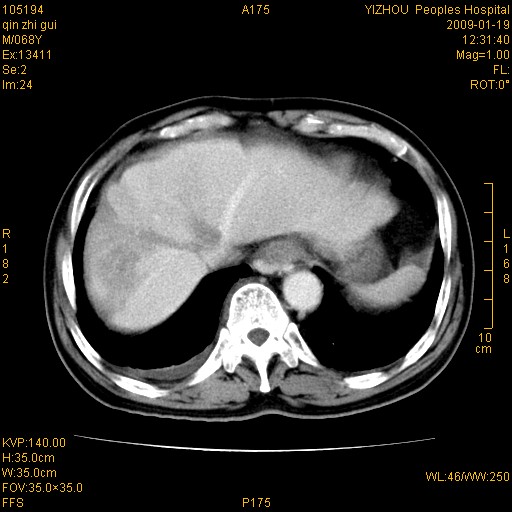

以下是引用随光逐影在2009-1-21 16:11:00的发言:[br]1)考虑肝右叶肝癌并肝静脉及门静脉瘤栓形成。2)肝硬化,少量腹水。3)胆囊炎。4)右侧少量胸腔积液。

病灶外缘凹凸不平,平扫低密度,增强动脉期有强化,门脉早显,静脉期及延期呈延迟强化,结合病史考虑右肝前叶巨块型肝癌可能性大,强化表现不除外胆管细胞癌